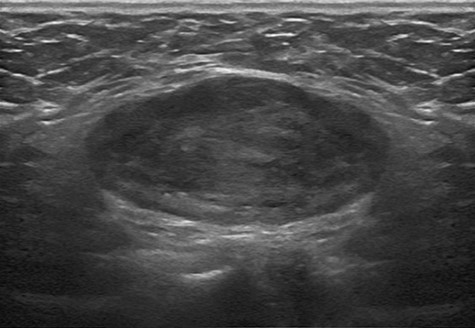

Ultrasonographic findings of the tumor in Case 1. A 9 × 3 cm hypoechoic, well-marginated mass was present in the left inguinal area.

A 35-year-old woman was admitted due to left inguinal swelling with an intermittent pain that had begun 3 months previously. The patient had no significant medical, drug, smoking, trauma, abdominal surgery or family history. Physical examination revealed an approximately 9-cm soft, movable mass with mild tenderness. Ultrasonography revealed a hypoechoic well-marginated 9 × 3 cm ovoid mass in the left inguinal area (Fig. 1). The operation was performed under general anesthesia with the patient placed in a supine position. A 5-mm incision was made through the umbilicus down to the midline fascia for 5-mm 30° camera port. Two 3-mm incisions were made on both lateral sides of the abdomen for the instrument insertion. Laparoscopy showed that the internal ring was occluded, and the mass was displaced into the peritoneal cavity when the inguinal area was pressed from the outside. The tumor was easily separated from the surrounding tissues, and complete intracorporeal excision of the tumor and posterior wall repair were performed (Fig. 2). The histopathological evaluation confirmed a solid, well-marginated mass described as a stromal cell proliferative lesion with multifocal vascular ectasia and tangles of smooth muscle bundles (Fig. 3). The pathological diagnosis was angioleiomyoma. The patient was discharged the next day. Postoperative pain improved daily, and there was no postoperative wound infection, bleeding, or fluid collection observed. The patient was followed up for 1 week, 1 month, 6 months and 1 year after the discharge. The surgical site was assessed by ultrasonography. There was no evidence of recurrence 12 months after the surgery.